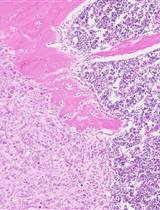

The figure from the original article is presented below (Figure 4).

Figure 4. Expression levels of PI3K/mTOR pathways' downstream components in mice's anterior prostate respond to Pten conditional knockout. This figure is adapted from the authors' published article, A Novel Controlled PTEN-Knockout Mouse Model for Prostate Cancer Study (Figure 2, Panels A–C). Frontiers in Molecular Biosciences [8]. (A) IHC staining to detect Cre recombinase in Pten LoxP/LoxP (L/L) mice's anterior prostate (AP) from different age groups that are infected with different adenovirus vectors. Ad-CMV-Luc, adenovirus vector that expresses luciferase using a cytomegalovirus (CMV) promoter. Green arrows indicate the basal cells. Green dash lines outline the stroma. Green triangles point toward stroma cells. Pten, phosphatase and tensin homolog deleted on chromosome 10. Ad-Cre-Luc, adenovirus vector that co-expresses luciferase and Cre recombinase (also using the CMV promoter). (B) IHC staining to detect Pten and downstream components of the PI3K/mTOR pathways in Pten L/L mice's AP that were infected with Ad-CMV-Luc and Ad-Cre-Luc viral vectors. Red arrows indicate Pten-, P-Akt-, P-S6-, or P-4E-BP1-positive cells. P-S6, phospho-S6 ribosomal protein. P-4E-BP1, phospho-eukaryotic translation initiation factor 4E-binding protein 1. (C) Serial IHC staining to detect Pten and downstream components of the PI3K/mTOR pathways in Pten L/L mice's AP at 0, 4, 8, and 16 weeks from the surgical delivery of the viral vectors. Red arrows indicate Pten-negative cells with activated P-S6 and P-4E-BP1.